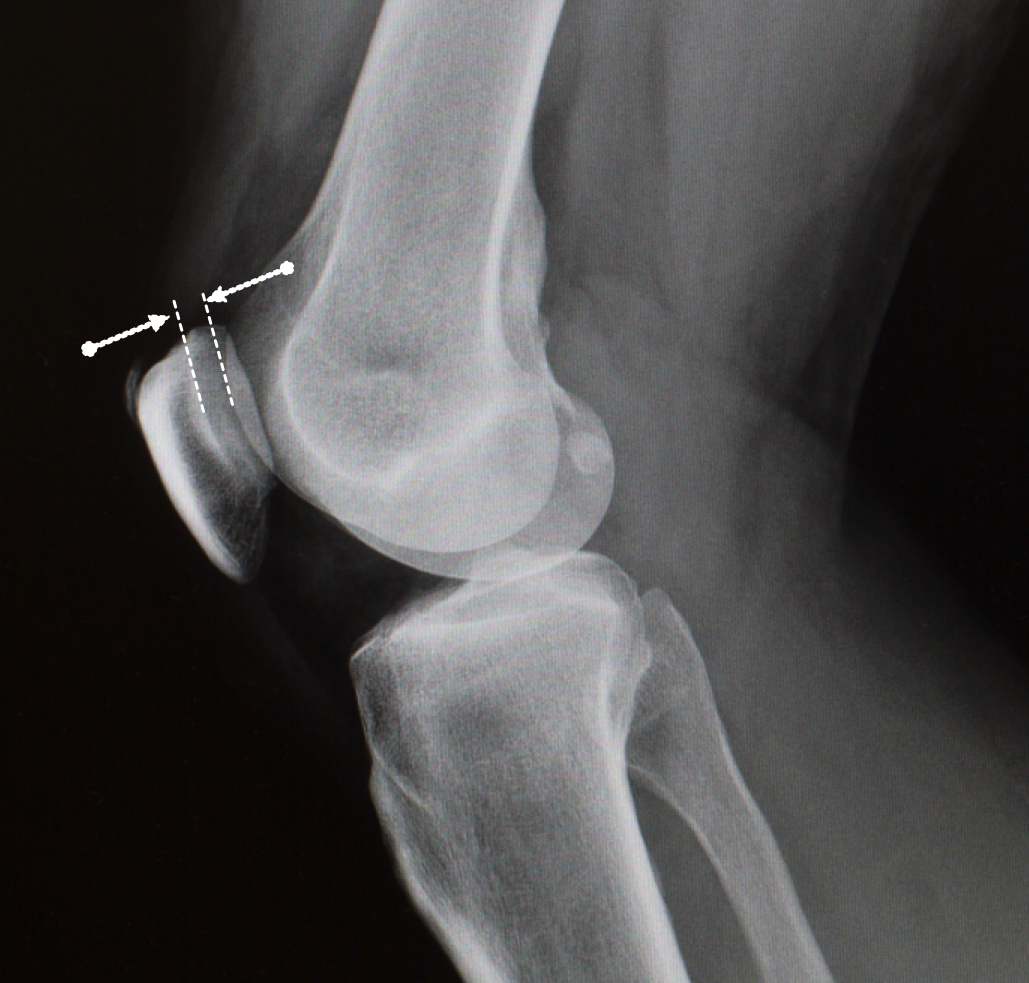

Osteoarthritis between the patella (knee cap) and femur (thigh bone) is also common. This lateral (side-on) X-ray shows a healthy gap between the patella and femur, meaning the articular cartilage still has a healthy thickness. A narrowing of this gap would indicate cartilage wear and osteoarthritis of the patella-femoral joint.